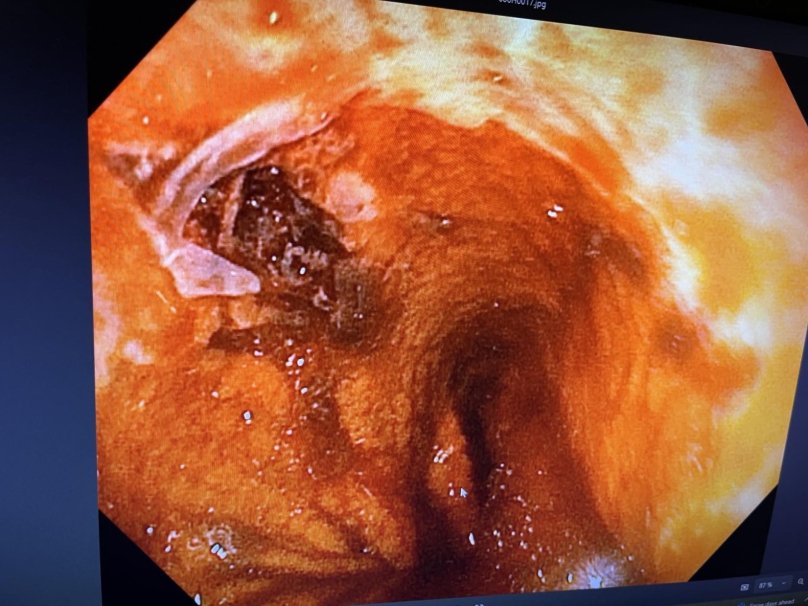

У Дрогобичі медики врятували 29-річного чоловіка, який поступив до лікарні у критичному стані з масивною шлунково-кишковою кровотечею. Причиною став синдром Маллорі-Вейсса — поздовжній розрив слизової оболонки в ділянці з’єднання стравоходу та шлунка. Про це повідомили у лікарні 19 лютого.

Як розповів лікар-ендоскопіст, завідувач діагностичного відділення Станіслав Шуцький, пацієнту оперативно виконали гастрофіброскопію  LVIV.MEDIA/static/sprite/symbol.svg#info"> . У місці з’єднання стравоходу зі шлунком медики виявили розрив слизової оболонки та пошкоджену судину.

«В ході маніпуляцій та завдяки введенню фізіологічного розчину, який «роздуває» тканини - було досягнуто ефекту перетискання пошкодженої судини. Таким чином кровотечу вдалось зупинити», — зазначили у лікарні.